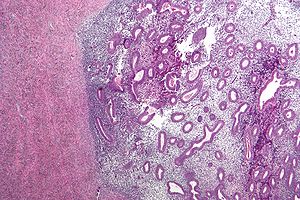

DDx:

- Adenocarcinoma - especially colorectal adenocarcinoma.

- Endosalpingiosis - does not have stromal component.

- In the GI tract, it classically expands the muscularis propria.